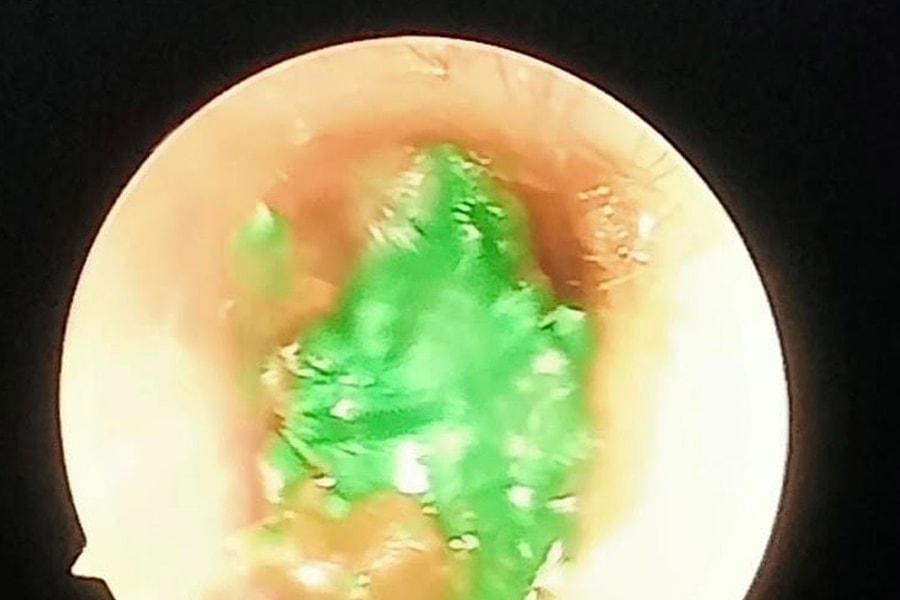

Anesthesia to remove foreign object from ear of 46-month-old patient in Nghia Dan

(Baonghean.vn) - Nghia Dan District Medical Center said that the unit received patient LDC (46 months old) to the hospital with earache, tinnitus... Through examination, the doctor discovered...

Successfully removed foreign object of clay in child's ear

(Baonghean.vn) - Nghia Dan Medical Center said that the unit received patient LDC (46 months old, in Nghia Lac commune) in the hospital with earache, tinnitus...